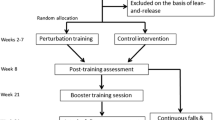

Twenty-six chronic stroke participants were categorized into high and low-functioning groups based on their Chedoke-McMaster-Assessment scores. All participants received a pre-training, slip-like stance perturbation at level-III (highest intensity/acceleration) followed by 11 perturbations at a lower intensity (level-II). If in early phase, participants experienced > 3/5 falls, they were trained at a still lower intensity (level-I). Post-training, immediate scaling and short-term retention at 3 weeks post-training was examined. Perturbation outcome and post-slip center-of-mass (COM) stability was analyzed.

Twenty six community-dwelling people with self-reported diagnosis of chronic (> 6 months) hemi-paretic, cortical stroke, confirmed by their physician, who were able to ambulate independently with or without an assistive device were included in the study. Participants were screened and excluded if they had cognitive impairment (≤ 26/30 on Montreal Cognitive Assessment Scale), aphasia (≥ 71/100 on Mississippi Aphasia Screening Test), low bone density (T score < − 1.5 on heel ultrasound), or presence of any other self-reported neurological, musculoskeletal, or cardiovascular condition. Clinical measures such as Berg balance test (BBS), Timed up and go test (TUG), 6 min walk test, 10 m walk test, and Chedoke-McMaster Stroke Assessment (CMSA) were performed to determine the baseline functional status and the severity of impairment. The demographic details of the participants are presented in Table 1. The study was approved by the institutional review board of the University of Illinois at Chicago.

Participants were divided into two groups, a high functioning and a low functioning group, depending on their level of impairment as assessed by the Chedoke-McMaster Stroke Assessment scale (CMSA). Based on the findings from a previous study demonstrating differences in CMSA leg and foot scores between individuals with failed and successful reactive stepping response, the leg score was used to divide participants into two groups (> 4 designated as high functioning and ≤ 4 as low functioning) [33]. Participants were instructed to assume a standing position with feet shoulder width apart on the Activestep treadmill (Simbex, Lebenon, NH) which would deliver the slip-like, forward perturbation. All participants donned a safety harness suspended from the treadmill arch in order to prevent a fall where their knees would touch the treadmill belt. They were instructed to expect an unannounced slip-like perturbation at any instance. Participants were asked to perform their natural response to recover from the perturbation and prevent themselves from falling. After familiarization trials, participants were subjected to a pre-training trial at the highest intensity (level III), followed by five perturbation trials given at one lower intensity (level II). During these trials, if participants experienced more than three falls, they were assigned to be trained at a lower perturbation intensity (level I), whereas the rest of the participants continued to receive the remaining training at level II to complete the protocol consisting of a total of 11 slip trials. Thus, those participants who did not tolerate the higher intensity were exposed to 11 more slips at a lower intensity (S1’-S8’; S9’-11′) whereas, for the participants who tolerated the high intensity, these 5 trials were considered a part of the high intensity training arm and they received 6 (S6-S8; S9-S11) additional trials at this intensity (Fig. 1a).

Following the initial eight slip trials, all the participants were made to walk at their self-selected natural speed for two trials which served as wash-out trials in order to reduce anticipation of the upcoming perturbation. After training, both groups were subjected to a post-training trial at the pre-training intensity (level III for high intensity training arm and level II for low intensity training arm) to examine scaling of the recovery response. Three weeks after training, participants from both groups were re-tested in order to assess the training retention. At this re-test, each participant received a single slip perturbation at the pre-training perturbation intensity (Fig. 1a). During the training and testing sessions, participants were intermittently asked if they experienced any pain, discomfort, fatigue or fear and would like to discontinue. All the participants consented to complete the protocol.